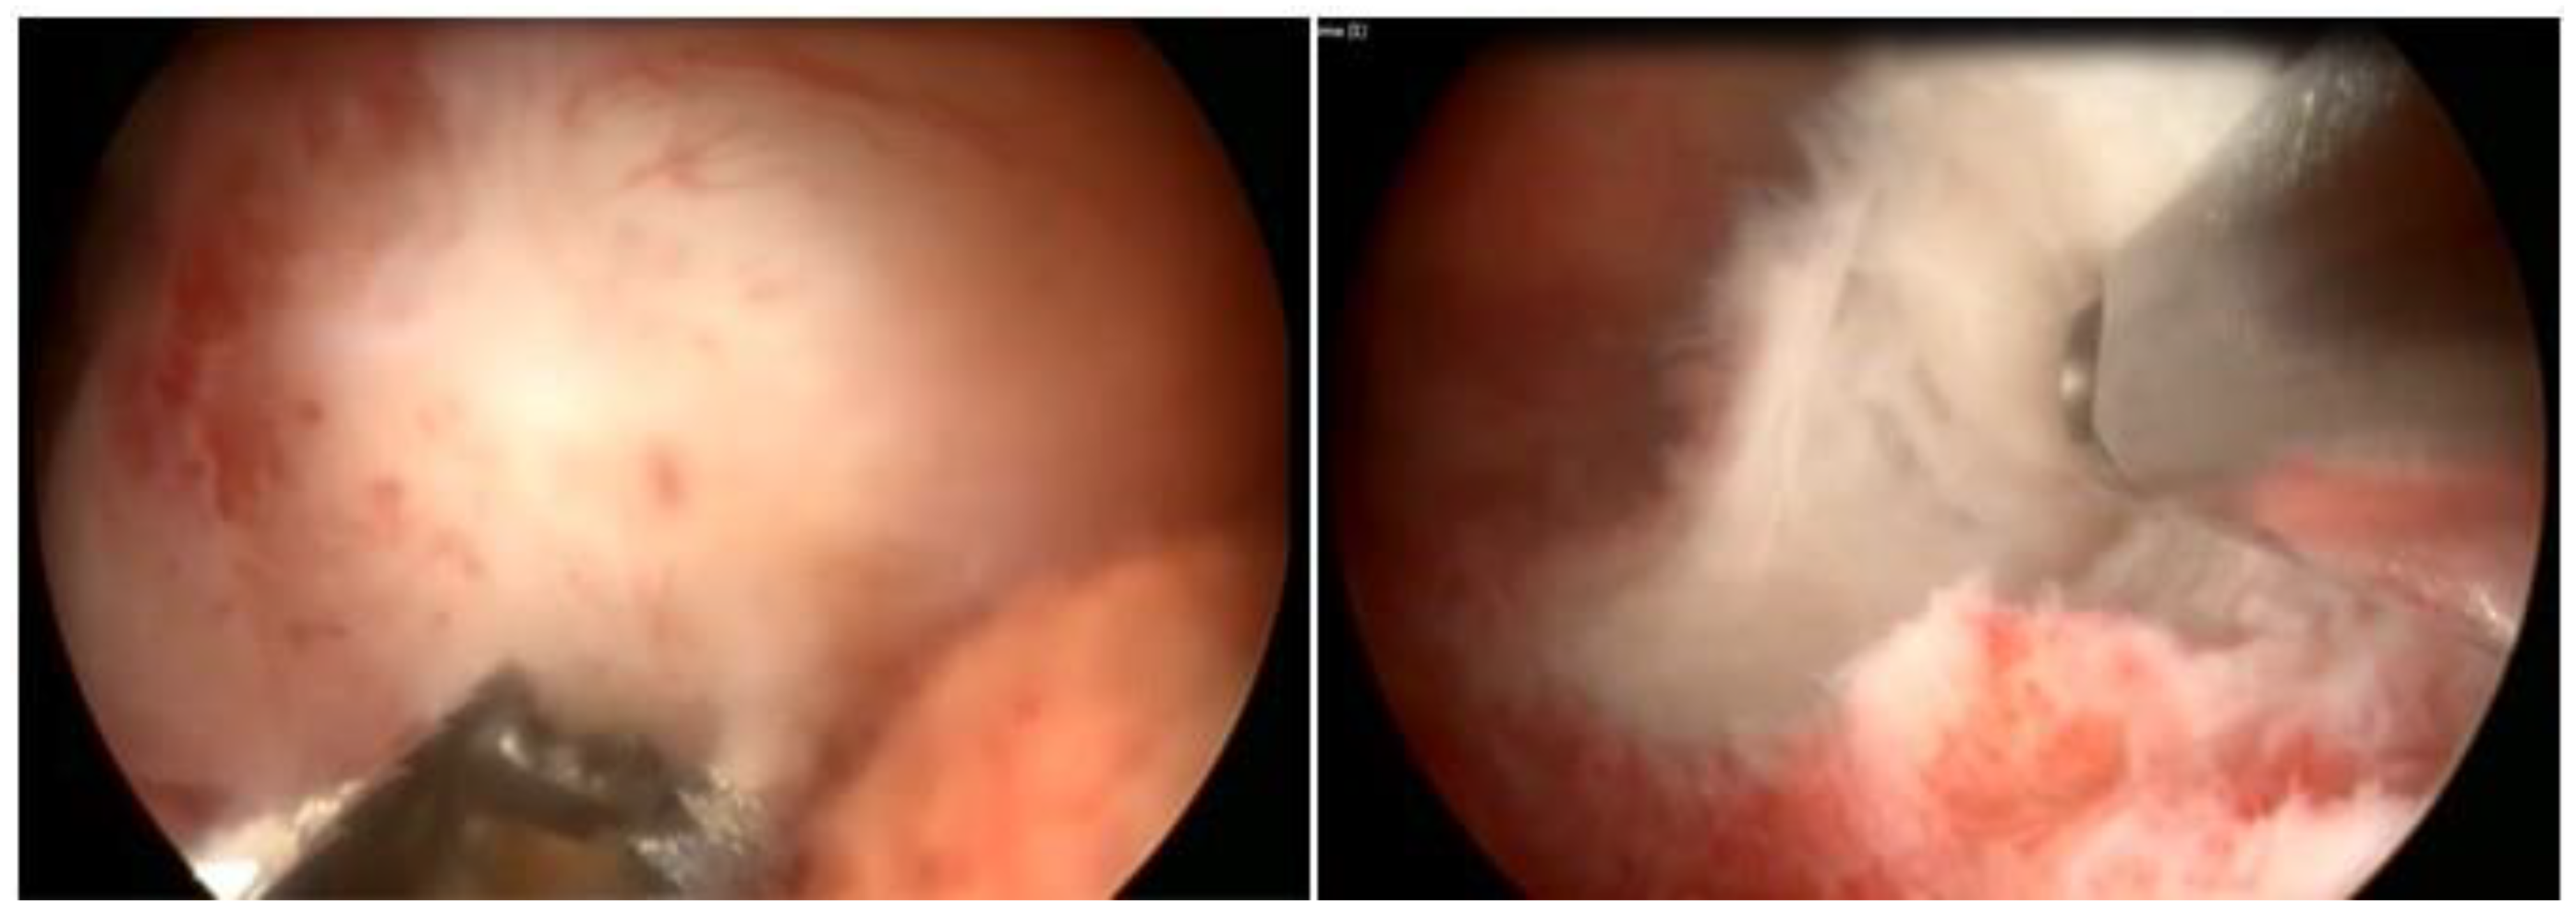

Hysteroscopy, as a method of direct visualization of the uterine cavity, offers all possible information about the intracavitary portion of the submucous myoma and a good assessment of the portion of the myoma, which is found in the myometrium, intramural portion. Thus, with hysteroscopy, it is possible to classify the submucous myoma and assess the need for other imaging methods. Another important function of hysteroscopy is to rule out other intrauterine causes of bleeding and to carry out an anatomopathological study of the endometrium or of the identified lesions, so it should, whenever possible, be indicated in the investigation (Figure 1).

Figure 1. Submucous myoma—hysteroscopic view.